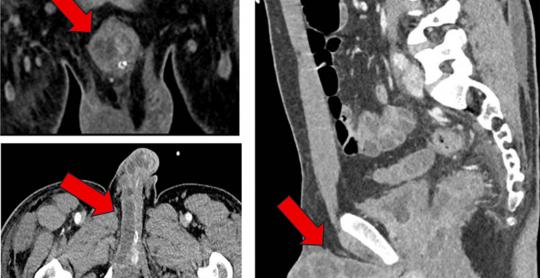

Journal of Medical Cases

Vol. 17, No. 5, May 2026, pages 183-189

By Jessica Thomas et al.